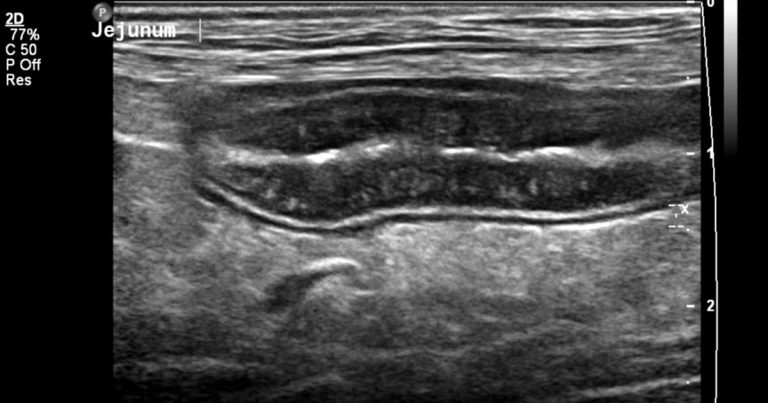

Diagnostic approach

The diagnostic approach is different for each patient, and based on the signalment, duration of the clinical signs and physical examination/clinical status, which will guide the extent and type of investigations.